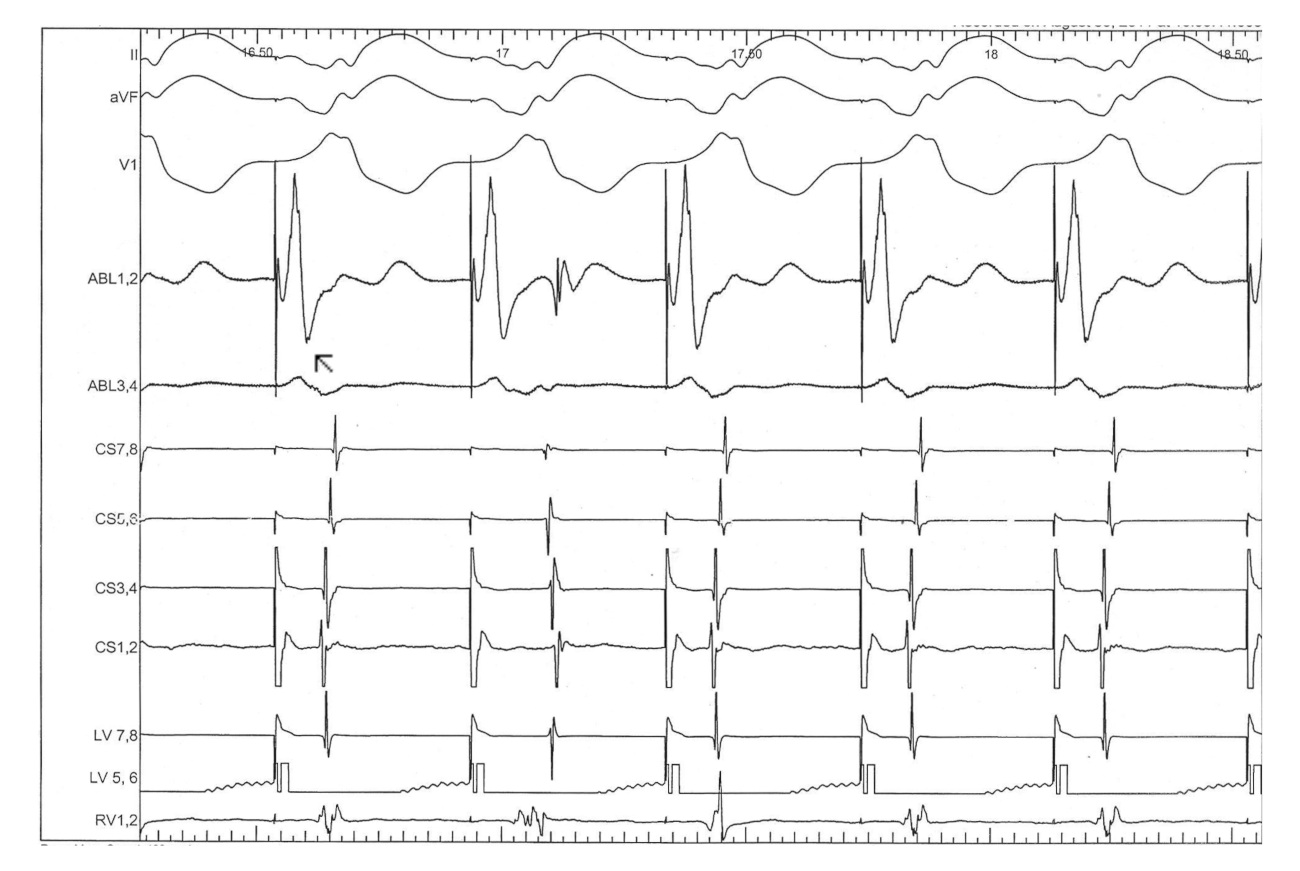

#10 Consider non annular location of AP

fig2.jpg

fig3.jpg